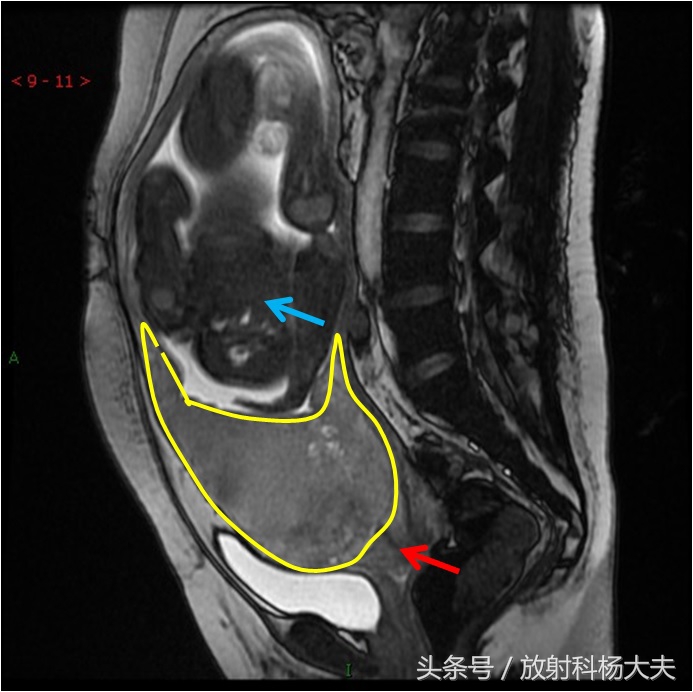

因此,临床大夫在怀疑产妇胎盘前置时,超声是必须的检查项目,MRI在胎盘前置的诊断上也显得越来越重要。一项研究发现对于前置胎盘MRI的诊断准确率为100%,而超声为79%。在正常情况下,胎盘在MRI上表现为均匀的中等稍高信号,同子宫和胎儿能明确区分。由于MRI影像对软组织分辨率极高,可全面显示胎盘及其周围组织的形态结构,尤其胎盘与子宫下段的附着程度加大,逐渐靠近宫颈口,且下缘低于胎儿先露部时,就能诊断。

图中黄线为胎盘,红箭为宫颈。蓝箭为胎儿。可见胎盘覆盖了宫颈。